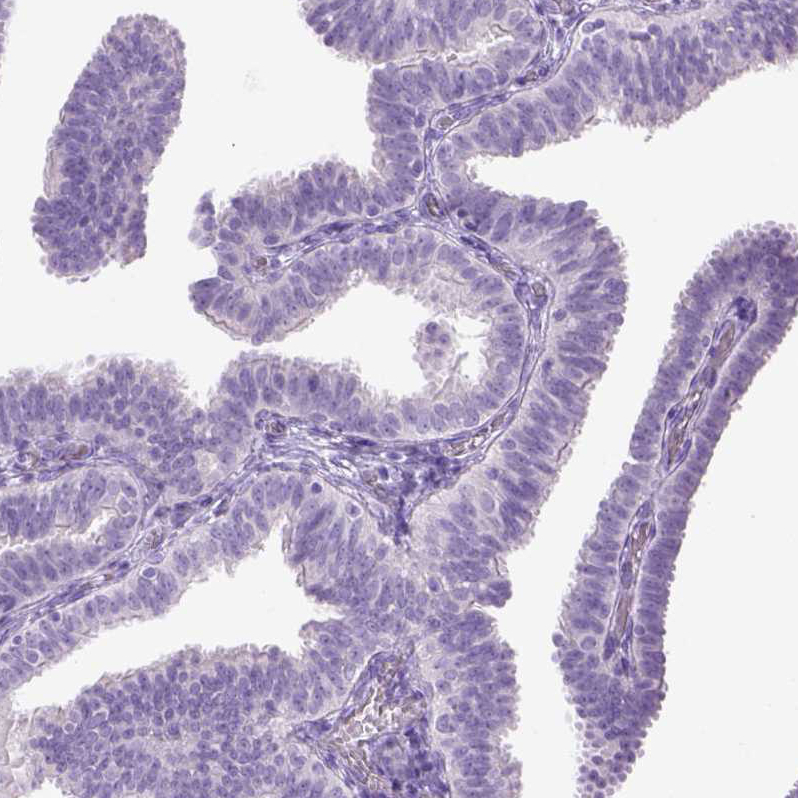

Immunohistochemistry analysis in human urinary bladder and fallopian tube tissues using HPA022261 antibody. Corresponding CYP24A1 RNA-seq data are presented for the same tissues.